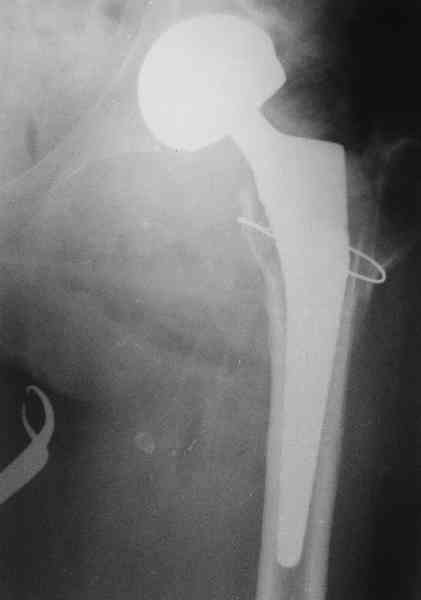

Не такое уж страшное укорочение по снимкам.Вчера прооперирован похожий

случай.Обошлись без релиза и аппаратного низведения. Укорочение было 4

сантиметра.Теперь ножки ровные.